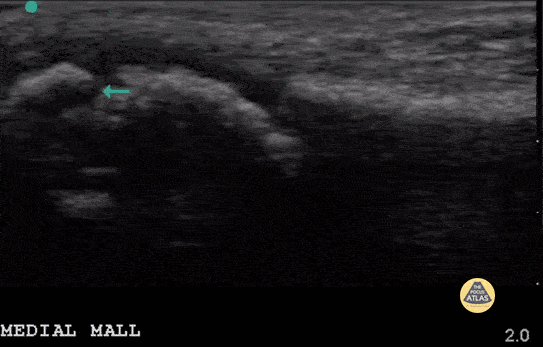

7 year old with medial malleolus avulsion fracture of the distal tibia. The green arrow points to the gap where the avulsion piece (left of screen) is detached. Note a physis also visible (mid screen). Contributor: Antonio Riera, MD